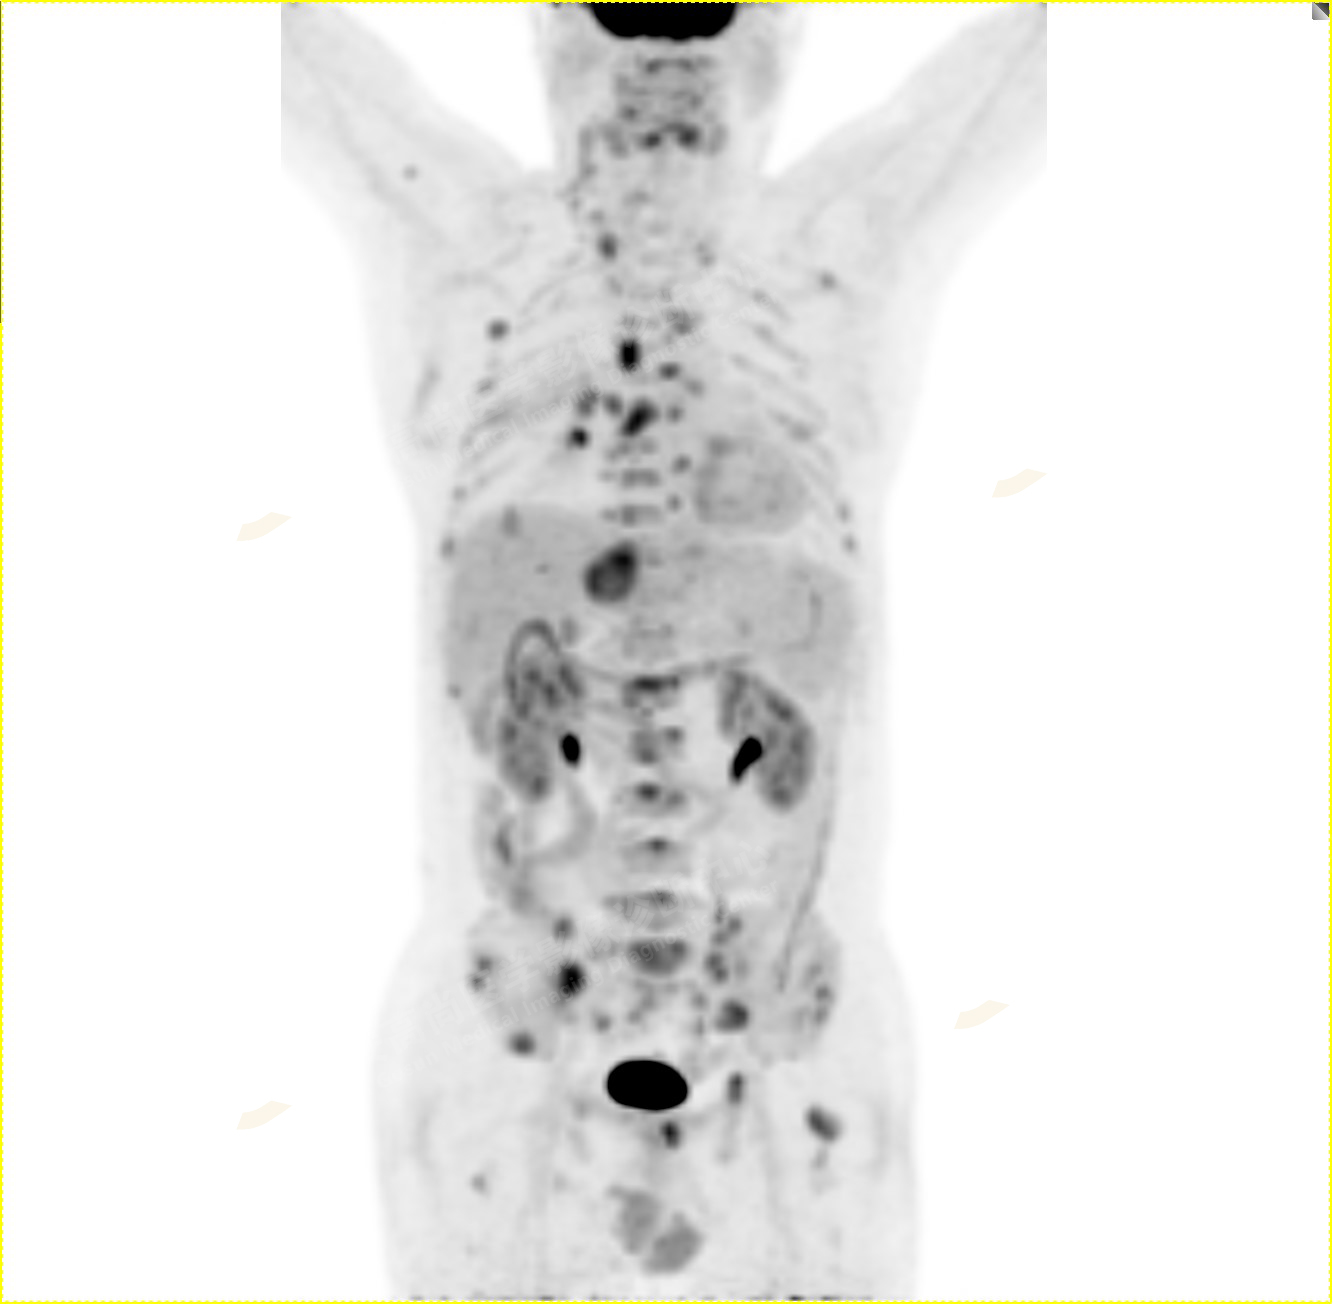

2.以下為全身多發(fā)轉移灶

2.雙肺內(nèi)彌漫性分布大小不等實性小結節(jié)灶及粟粒狀高密度影,均未見FDG代謝明顯異常增高,均多考慮為癌性淋巴結炎及轉移性病變。

3.右側頸部(Ⅱ-Ⅴ區(qū))、右側腋窩區(qū)、右側肺門及縱隔(1R、1L、2、4、6、7組)、肝門區(qū)多發(fā)腫大淋巴結,呈不同程度異常增高,均考慮為淋巴結轉移。

4.肝S4、8段團塊狀及結節(jié)狀低密度病變,以S4段病變?yōu)橹什煌潭菷DG代謝異常增高,考慮為肝多發(fā)轉移。

5.右側肱骨上段、左側肩胛骨、右側鎖骨胸骨端、胸骨、雙側多發(fā)肋骨、脊柱多發(fā)椎體及附件、雙側髂骨、雙側髖臼、雙側恥骨、雙側肱骨上段多發(fā)成骨性病變,呈不同程度FDG代謝異常增高,考慮為多發(fā)骨轉移瘤。

以上病變符合:T4N3M1c,ⅣB期(UICC/AJCC,2018年第8版肺癌TNM分期)。